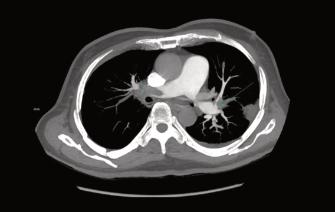

EnCDIcontamosconlatecnologíaparalarea‐lizacióndeestudiosdiagnósticos,asegurando unacorrectaevaluacióndelospacientes.(Fig 3y4).Estopermitirálaidentificaciónprecoz depotencialescomplicacionespulmonares post-COVID-19,conelfindequeelmédico tratanteproporcioneeltratamientoadecuado yevitarsecuelasposteriores.